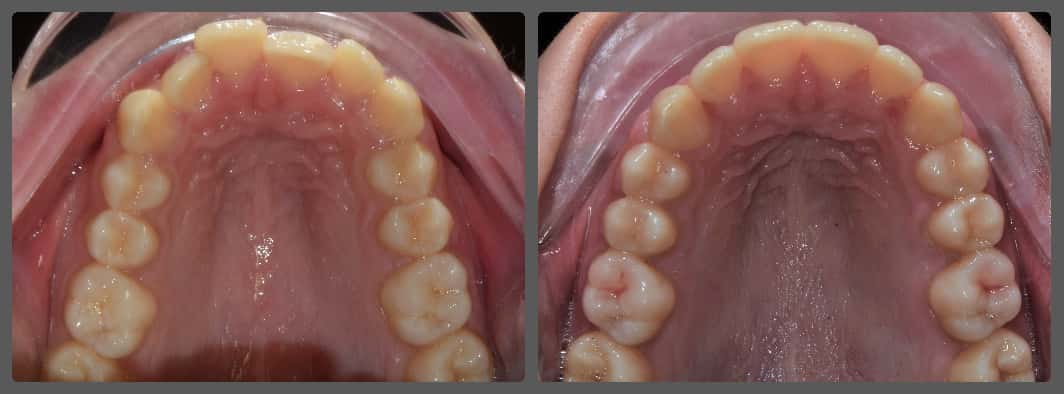

Extrém súlyos alsó-felső torlódása miatt jött hozzám fogszabályozási konzultációra Viki. A korábbi szakvélemények mindegyike foghúzással járt volna. Súlyosan eltolódott alsó-felső középvonalat, súlyos alsó-felső torlódást, mélyharapás, fogívszűkületet és a nyelv felé dőlő fogíveket diagnosztizáltam. Viki harapási és anatómiai adottságai miatt úgy ítéltem meg, hogy a kezelését foghúzás nélkül is végig tudjuk vinni. H4 önligírozó fogszabályzó készüléket ragasztottunk Vikinek, és a torlódott területeken tolórugóval csináltunk helyet a fogívből kiszorított fogaknak. A harapás harmonizálást és a mélyharapás korrekcióját intermaxilláris gumihúzással, valamint harapásemelőkkel végeztük. A teljes kezelés 26 hónapig tartott, melynek végére egy igazán gyönyörű, telt mosolyt sikerült Viki arcára varázsolni, mindemelett a szinte tökéletes oldalsó fogilleszkedést is megtartottuk, tovább javítottuk. Az ilyen látványos változások, páciens átalakulások miatt szeretem a legjobban a munkám!